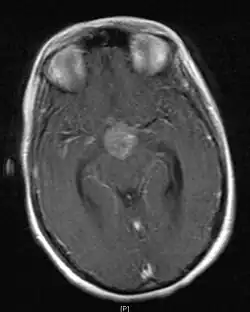

• Mainly located in midline structures, suprasellar region or pineal gland, also basal ganglia and hypothalamus

Location

• Toronto; 2006 (1995-2004) PMID 16530340 -- "Limited-field radiation for bifocal germinoma." (Lafay-Cousin L, Int J Radiat Oncol Biol Phys. 2006 Jun 1;65(2):486-92.)

• Retrospective. 6 patients with bifocal germinoma (pineal + suprasellar). All with diabetes insipidus at presentation. Treated with chemo followed by limited-field RT (whole ventricle 24-40 Gy +/- boost). Median F/U 4 years

• Outcome: 100% complete remission

• Conclusion: Bifocal germinoma can be considered locoregional rather than metastatic disease